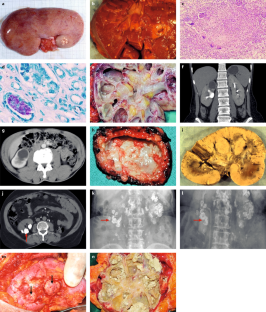

Merchant, S., Bharati, A. & Merchant, N. Tuberculosis of the uro-genital system — urinary tract tuberculosis: renal tuberculosis. I. Indian J. Radiol. Imaging 23, 46–63 (2013).

Merchant, S., Bharati, A. & Merchant, N. Tuberculosis of the uro-genital system — urinary tract tuberculosis: renal tuberculosis. II. Indian J. Radiol. Imaging 23, 64–77 (2013).

Muttarak, M., ChiangMai, W. N. & Lojanapiwat, B. Tuberculosis of the uro-genital tract: imaging features with pathological correlation. Singapore Med. J. 46, 568–574 (2005).

Jung, Y. Y., Kim, J. K. & Cho, K. S. Uro-genital tuberculosis: comprehensive cross-sectional imaging. AJR Am. J. Roentgenol. 184, 143–150 (2005).

Gaudiano, C. et al. Multidetector CT urography in urogenital tuberculosis: use of reformatted images for the assessment of the radiological findings. A pictorial essay. Abdom. Radiol. 9, 2314–2324 (2017).